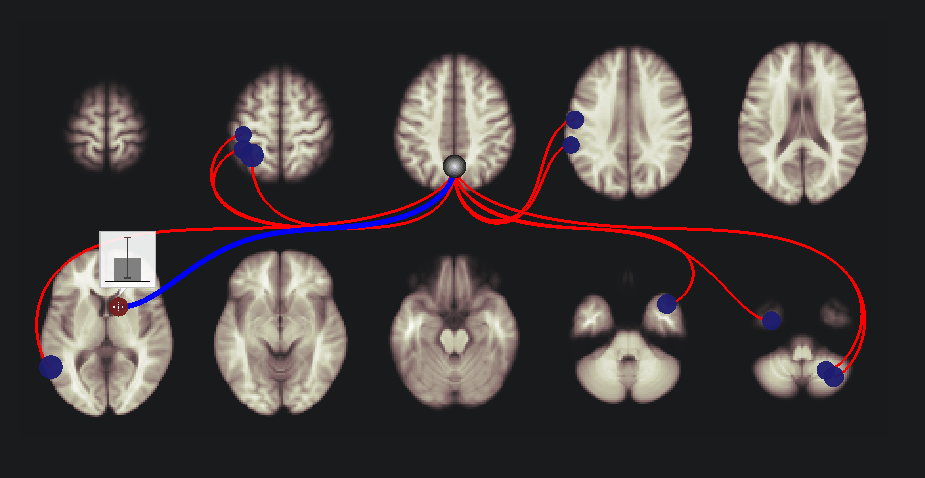

connを用いてfMRIによる脳機能結合の解析を行い始めたところです。初歩的な質問で恐縮なのですが、connでROI to ROIの機能結合を行って、結果を図に示したときに、TargetのROIが青と赤で示され、これが、正と負の相関であることはわかるのですが、SeedとROIのconnectionの線の色が、赤と青に区別されている意味がわかりません。ご教授していただけると幸いです。お忙しいところ誠に申し訳ありませんが、どうかよろしくお願いいたします。

赤い点と青い点があり、そして、赤い線と青い線があるわけです。

点:これは検定結果のEffect sizeを示しています。(connectivityではなく、検定結果を反映しています)

線:connectivityの絶対値が一番大きいものを示しています。

これを理解するうえで、一番左下の脳の2つの点(青と赤の点)に着目してみます。

まず、青い点をクリックしてみてください。

そうすると、点の上に棒グラフが表示されます。

そうしたら、画面の下の方にある “plot effects” をクリックしてみてください。

そうすると、以下のような図が出力されます。ここでは、年齢との相関をみていますので、この領域において、Effect sizeが-0.06弱ということがわかります。

続いて、plot effects の右側にある “plot values” をクリックしてみてください。

この例では、全体的には負なのですが、ひとつだけ +0.77のものがあり、それが一番大きいので、線は赤色になっています。

次に、その右側にある赤色の点をクリックしてみます。

そして、先ほどと同様にplot effectsを押します。

今回はeffect sizeが0.02よりちょっと大きいぐらいということがわかります。

(とりあえず説明のためにp値をものすごくゆるめているので値はあまり気にしないでください)

そして、plot valuesをクリックします。

そうすると、絶対値が大きいものは、-0.42となります。なので、青線です。

ということで繰り返しになりますが、

点:検定結果のEffect sizeで、正ならば赤、負ならば青となります。

線:各被験者のconnectivityの値で絶対値が一番大きいものを反映し、正ならば赤、負ならば青となります。

これでいかがでしょうか?